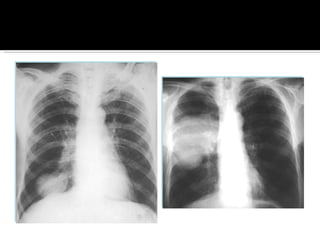

Placa de toráx. Citología de 3 muestras.  Para pacientes con factores de riesgo. EN POBLACION DE ALTO RIESGO: Mayor proporción de lesiones tempranas y resecables No se demostró efecto en Mortalidad Por lo que no se recomienda un programa de escrutinio en Población abierta.

Historia clínica Examen físico Lab  BH,QC Citología seriada esputo. Broncoscopia [biopsia] Medistianoscopia [afección ganglios] Rx AP y lateral. TAC   pulmones, mediastino, hígado, suprarrenales. PET   metástasis. No detecta <15mm.  RM cerebro si hay metástasis. Gammagrama óseo.

Placa de toráx.Citología de 3 muestras. Para pacientes con factores de riesgo. EN POBLACION DE ALTO RIESGO: Mayor proporción de lesiones tempranas y resecables No se demostró efecto en Mortalidad Por lo que no se recomienda un programa de escrutinio en Población abierta.

Historia clínica Examenfísico Lab  BH,QC Citología seriada esputo. Broncoscopia [biopsia] Medistianoscopia [afección ganglios] Rx AP y lateral. TAC  pulmones, mediastino, hígado, suprarrenales. PET  metástasis. No detecta <15mm. RM cerebro si hay metástasis. Gammagrama óseo.